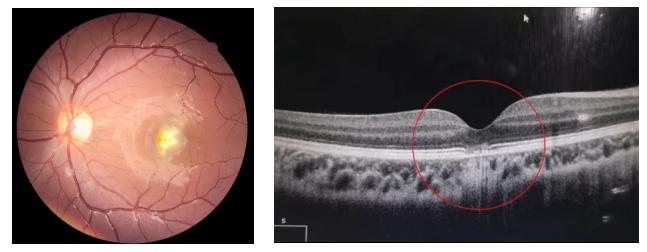

近期,浦东新区眼病牙病防治所门诊接诊了一名10岁男性学生,就诊原因为左眼突然看不清东西。经追问病史发现该学生使用了激光笔,检查后发现激光笔损伤视网膜,造成视力突发性下降。

图为受伤小男孩的眼底照相和OCT检查1

2、激光的辐照度大,会引起视网膜的灼伤。黄斑区位于视网膜中央,是视力最敏锐的区域,负责视觉和色觉的视锥细胞就聚集于该区域。任何累及黄斑部的病变都会引起中心视力的明显下降、视物色暗、变形等。